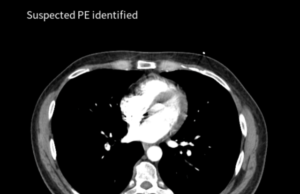

Thrombolex and Aidoc announce strategic partnership to advance breakthrough PE treatment

Thrombolex and Aidoc have announced a strategic partnership aimed at revolutionising the treatment of acute pulmonary embolism (PE), a press release reports.

This strategic collaboration,...

Adoption of AI into workflow associated with faster time to assessment...

An abstract presented at the 2024 American Venous Forum (AVF) annual meeting (March 3–6) revealed that, in the treatment of patients with pulmonary embolism...

New clinical data support AI solution for improved PE detection and...

Viz.ai has announced new clinical data supporting advancements in pulmonary embolism (PE) detection. Two studies have demonstrated the real-world clinical efficacy of Viz.ai’s PE module to...

Viz.ai reveals launch of new AI-powered modules for pulmonary embolism, aortic...

Viz.ai—a company focused on artificial intelligence (AI)-driven intelligent care coordination—today announced the U.S. commercial launch of its AI-powered modules for pulmonary embolism (PE) and...

AI triage solution for PE and aortic dissection receives FDA clearance

Medical imaging artificial intelligence (AI) specialist, Avicenna.AI, recently announced that it has received certification in the U.S. and European Union (EU) for CINA CHEST, its...